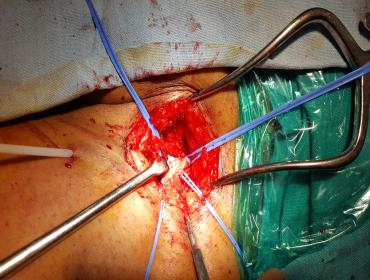

Endophlebectomy